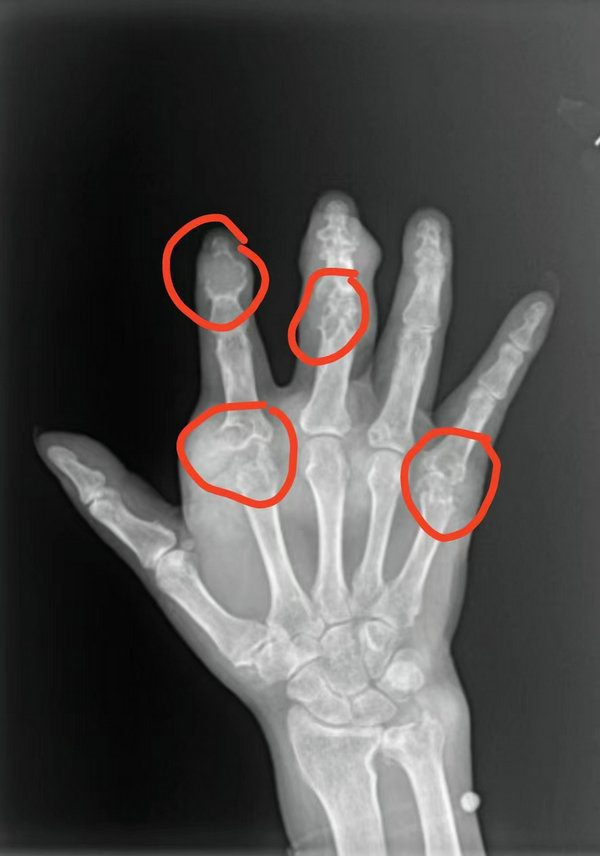

一位年过六旬的老人,发现高尿酸病史30年余,慕名来到郑州大学五附院骨科一病区住院手术治疗。在完善术前相关检查后医生通过X线片发现他的双手多处指骨及腕关节骨质已被侵蚀,部分可能已经出现病理性骨折。评估患者基本情况后,再次行多发痛风结节切除术。手术顺利,麻醉满意,术后手术切口愈合良好,患者顺利出院。

术前“虫”蚀样骨质